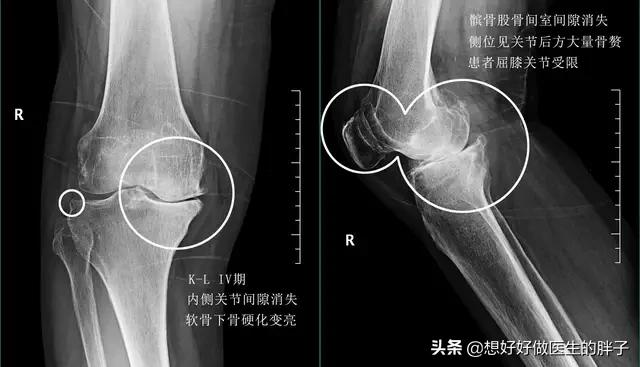

但是如果磨损进一步的加重,那么就会出现软骨的剥脱碎裂,患者的疼痛可能就会越来越严重,在此阶段的患者通常会走平路的时候,也会有明显的疼痛,做x线检查,基本会发现关节间隙已经开始出现了狭窄,而且会有骨赘也就是骨刺的形成。

当病程进行到了晚期,患者关节间隙会越来越严重,关节也会随之出现明显的变形,有的老年人会出现明显的o型腿,或者是x型腿的改变,基本都是源自于关节内软骨的磨损,导致的关节畸形。而患者呢,也会出现明显的关节疼痛,严重影响患者的生活质量,有一些患者会出现明显的夜间痛以及休息痛。

晚期骨关节炎:晚期骨关节炎由于患者已经出现了明显的关节畸形,很多患者已经谈不上生活质量,被折磨的痛不欲生,那么此时可能进行手术治疗的办法是最好的措施。过去主要采取的办法是比较单一的,我们称之为全膝关节表面置换术,也就是像膝关节软骨已经磨损殆尽的表面替换成金属表面,关节内的骨骼就不会发生直接的摩擦,疼痛也就会消失。